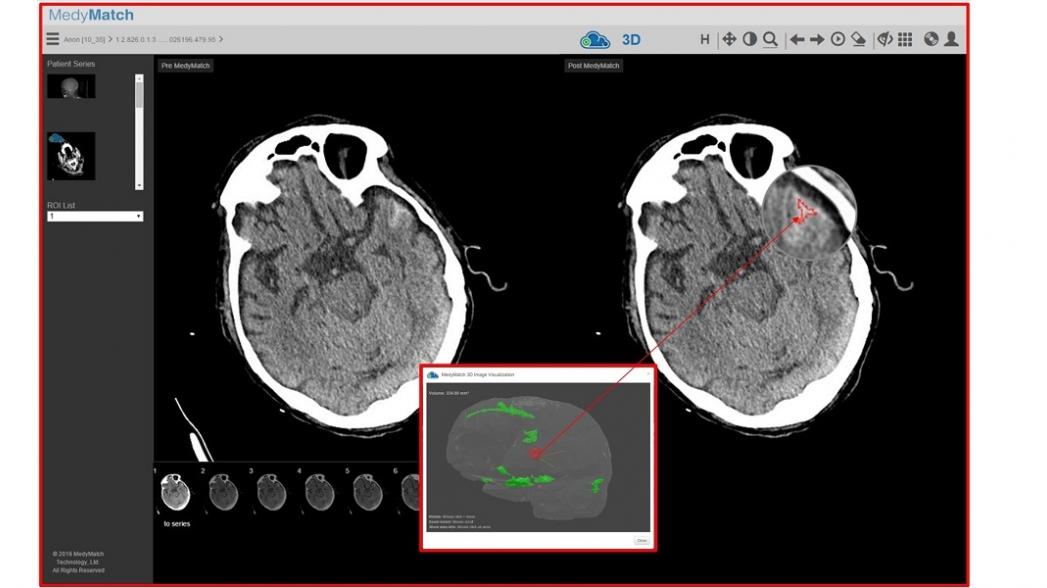

Решение MedyMatch предназначено для того, чтобы помогать врачам идентифицировать регионы в мозге, где возможно есть кровоизлияние. Когда пациенту делают сканирование с помощь компьютерной томографии, снимок отсылается в облачную систему для обработки, где платформа MedyMatch использует алгоритмы глубокого обучения, данные пациента и клиническую аналитику для того, чтобы обнаружить область кровоизлияния. При этом система сравнивает снимки с сотнями тысяч аналогичных изображений других пациентов, хранящихся в базе знаний и очень быстро фиксируются практически любые отклонения от нормального КТ-изображения мозга.

По утверждению представителей компании MedyMatch, их система способна обнаруживать неправильности в изображении мозга точнее, чем это делает человек. В результате система выдает трехмерные изображения с обнаруженными повреждениями мозга, которые позволяют врачам принимать более информированные решения.